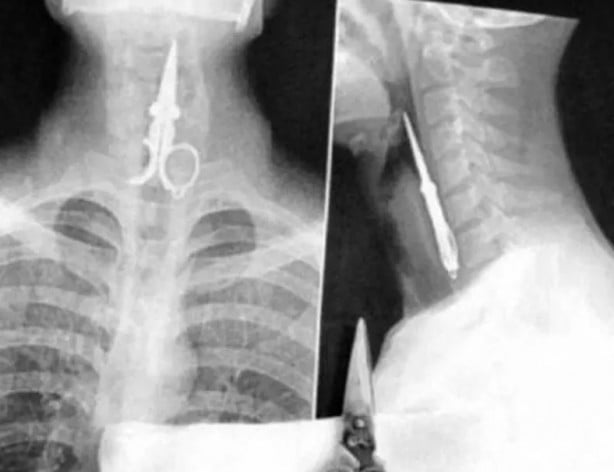

İşte görenleri şaşırtan o röntgen filmleri...